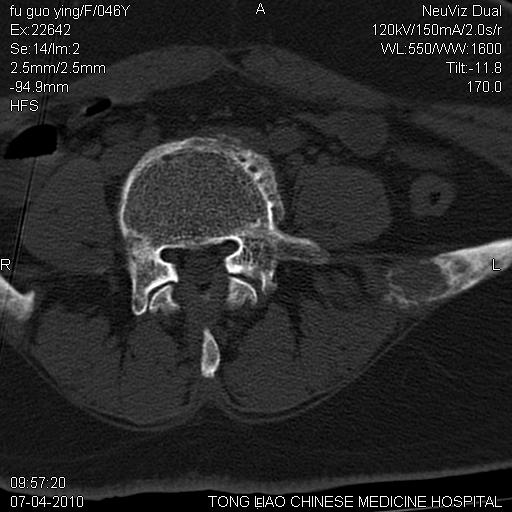

标题: CT27489:患者腰疼,其余椎体未见异常! [打印本页]

标题: CT27489:患者腰疼,其余椎体未见异常!

转移?

髂骨考虑转移瘤 椎体病变不像转移瘤

转移瘤

女性46岁,左髂骨溶骨性破坏+软组织肿块,考虑转移瘤,腰椎为退变/增生硬化/软骨下骨囊变。

不排除多发性骨转移瘤可能;建议行进一步检查。

考虑转移瘤可能性大

考虑转移瘤可能性大 ,建议查原发灶。

骨转?骨髓瘤?

不排除多发性骨转移瘤可能;建议行进一步检查及查原发灶。